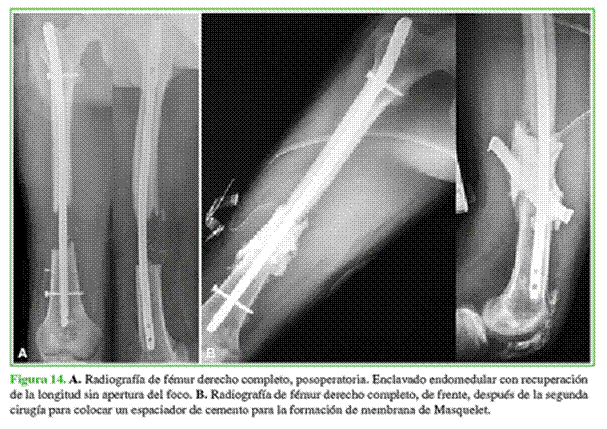

Hombre de 22 años, derivado al hospital con valva de yeso a las cinco semanas de haber sufrido un accidente automovilístico. Tenía una fractura diafisaria de fémur expuesta por la cara anterior con defecto segmentario de aproximadamente 10 cm, fractura conminuta de rótula homolateral (Figura 13) y lesión en el plexo braquial.

Al ingresar, se procedió a la revisión de la herida de la fractura expuesta y se decidió colocar una tracción esquelética por cinco días ante el marcado acortamiento del miembro.

Antes de la cirugía definitiva, se colocaron un enclavado endomedular para igualar la longitud del miembro y un espaciador de cemento con vancomicina-gentamicina; se administró tratamiento antibiótico por vía oral (Figura 14). A los cuatro meses, se procedió al recambio del espaciador con toma de muestras, que fueron negativas. A las dos semanas, se realizó la cirugía reconstructiva (Figura 15).